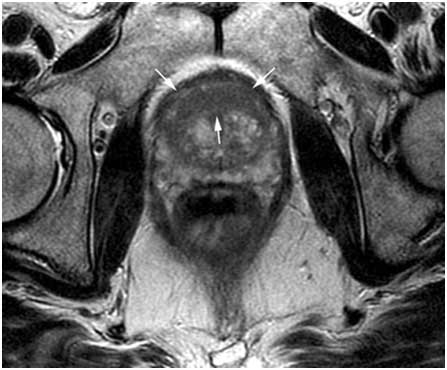

Diagnosis Prostate Cancer

- Prostate cancer kills over 10,000 men in the UK every year.

- MRI can solve this problem effectively

Images from the MRI scanner allow the surgeon to track the needle and to guide the tip into a target in the prostate. By using our Prostate Biopsy Robot, the surgeon controls the robot “remotely”, thus improving safety and accuracy. The robot can extract cells from the prostate within 2mm.